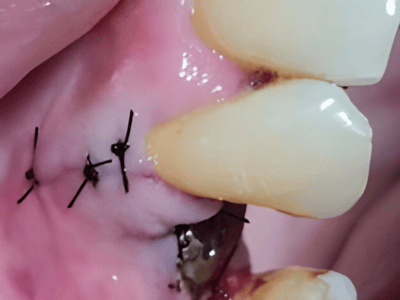

Dr. Deeksha Bhardwaj is a highly skilled dental specialist in Greater Noida, specializing in

Periodontics, Dental Implants, and Advanced Gum Care. With a BDS and MDS in Periodontics, she

provides expert treatment for gum diseases, receding gums, and dental implant procedures using the

latest technology.

Dr. Bhardwaj holds a BDS and MDS in Periodontics, specializing in gum health, dental implants, and advanced periodontal care.

Dr. Bhardwaj specializes in Periodontics, offering treatments for gum diseases, dental implants, laser dentistry, root canal treatments (RCT), teeth whitening, smile makeovers, and general dental care.